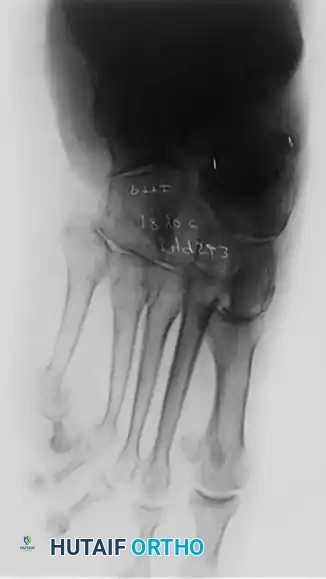

Clinical Pearl: The loss of the medial longitudinal arch can occur at the talonavicular, navicular-cuneiform, or cuneiform-metatarsal articulations. A weight-bearing lateral radiograph may initially show no bony collapse, appearing identical to the asymptomatic contralateral foot, even in the presence of obvious clinical pes planus.

- Radiography: Degenerative arthritic changes are visible in the subtalar and/or talonavicular joints.